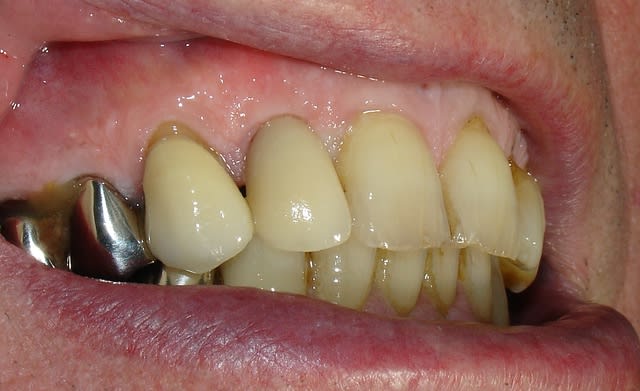

Quelques images de l'année dernière

Couronne en place mfxepr - Eugenol